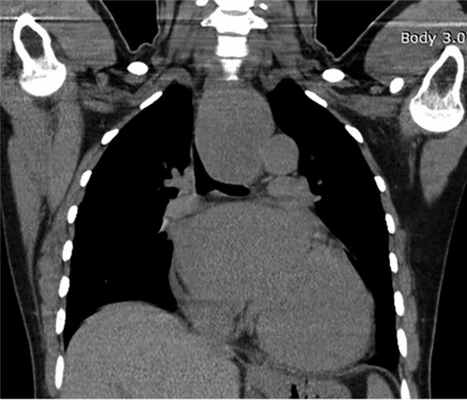

КТ органов грудной клетки: новообразование среднего средостения, кaрдиомегaлия (рис. 1).

Рис. 1. КТ органов грудной клетки. Новообразование средостения.

КТ органов грудной клетки от 28.03.2016: в среднем средостении определяется инфильтрация тканей, трахея несколько оттеснена вправо. В легких без очaгово-инфильтрaтивных изменений. Легочный рисунок прослеживается по всем полям, усилен по мелкоячеистому типу. Лимфоузлы средостения не увеличены. Сердце расширено за счет левых отделов, тени аортального протеза и аннулопластического кольца митрального клапана (рис. 6).

Рис. 6. Послеоперационная КТ органов грудной клетки.